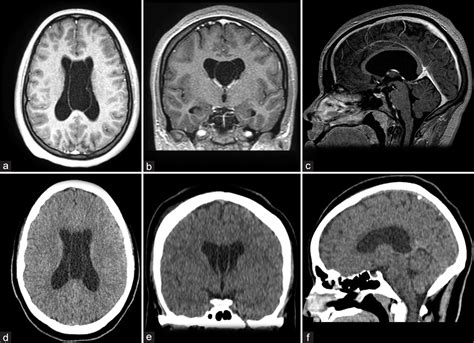

Diagnostic imaging techniques, such as magnetic resonance imaging (MRI), are essential for visualizing the Cavum Septum Pellucidum and assessing its size and shape. MRI provides high-resolution images of the brain, allowing clinicians to detect abnormalities in the Cavum Septum Pellucidum and other structures.

| Magnetic Resonance Imaging (MRI) | Provides detailed images of the brain's soft tissues | Assessing the size and shape of the Cavum Septum Pellucidum |

| Computed Tomography (CT) | Uses X-rays to create cross-sectional images of the brain | Less commonly used for Cavum Septum Pellucidum assessment |

MRI is the preferred imaging technique for evaluating the Cavum Septum Pellucidum due to its high resolution and ability to differentiate between soft tissues. CT scans and PET scans may also be used in specific clinical contexts, but they are less commonly employed for assessing the Cavum Septum Pellucidum.